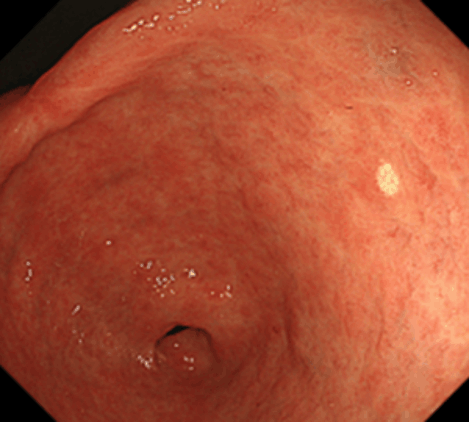

胃上皮下病変とは、胃の上皮(粘膜表層)の下の粘膜固有層(粘膜深層)や粘膜下層、固有筋層などに由来する腫瘤の総称です。以前は粘膜下層と固有筋層に局在する消化管間質腫瘍(GIST)、神経鞘腫、平滑筋腫、脂肪腫、迷入膵などを総称して粘膜下腫瘍(SMT)とすることが多かったのですが、近年は胃神経内分泌腫瘍などの、粘膜下層よりも浅層の粘膜固有層に主座を置く病変なども含めて、上皮下病変(SEL)とするのが一般的となりつつあります。本項では、従来のSMTに相当する病変について解説していきます。胃神経内分泌腫瘍については、別項をご参照ください。